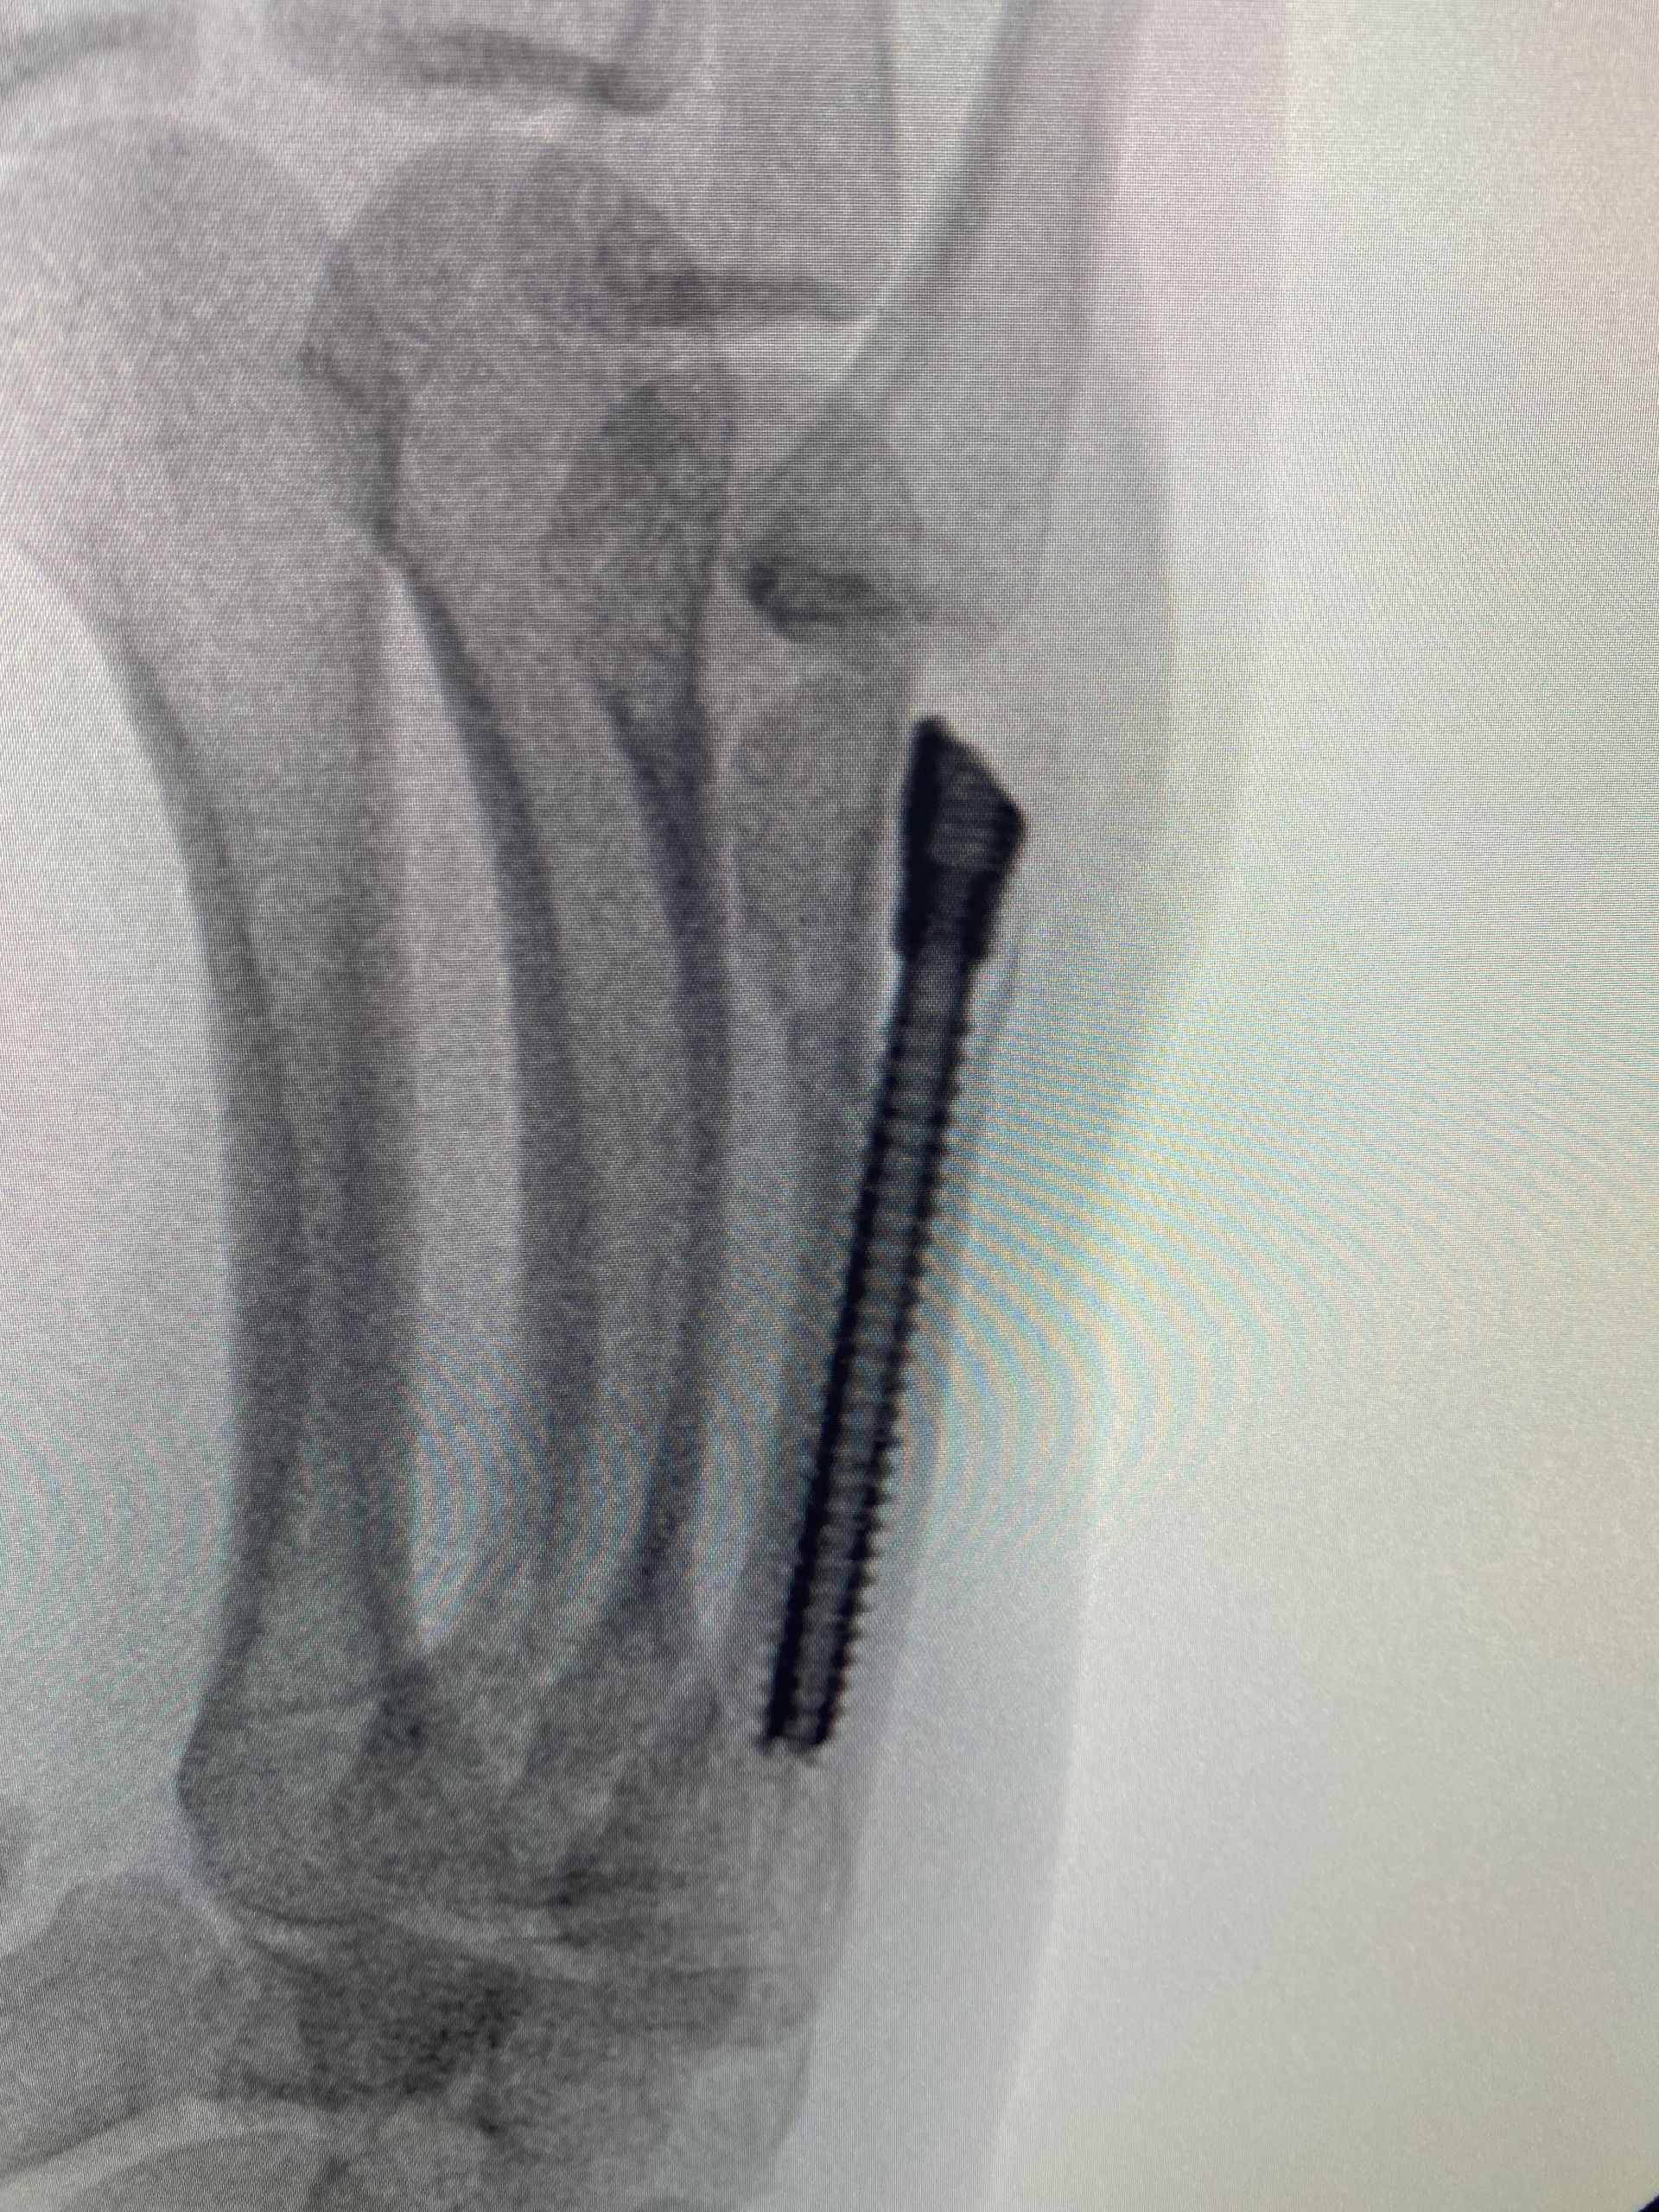

A técnica de parafuso intramedular é menos invasiva e foi descrita pela primeira vez em 2010, por Boulton et al. A técnica é minimamente invasiva e consiste em realizar uma incisão sobre o tendão extensor, no nível da articulação metacarpofalangeana, introduzir um fio guia e um parafuso intramedular de modo retrógrado. A fixação é rígida o suficiente para permitir movimentação ativa precoce, além de haver mínima dissecção de partes moles, menor risco de aderência tendínea, ausência de proeminência de material de síntese e ausência do risco de infecção das hastes expostas.

Em uma meta-análise realizada em 2019, Beck et al. avaliaram 169 pacientes e os resultados foram surpreendentes: 100% de união da fratura, 96% de recuperação de força de preensão palmar, 86° de flexão da articulação metacarpofalangeana e poucas complicações descritas. A crítica acerca de tal técnica cirúrgica é a violação articular por conta do acesso para introdução do parafuso. Mas a literatura não mostrou evidências de que esse ponto de introdução do parafuso traga malefícios ou prejuízos funcionais.

Em uma publicação de 2013, após análise tomográfica, foi comprovado que há apenas 12% de contato entre a base da falange proximal e o ponto de entrada do parafuso, dada a sua introdução dorsal (mesmo com a articulação metacarpofalangeana em completa extensão).

Sequência de imagens evidenciando fratura de colo do 5° metacarpo, desvio rotacional do 5° raio, redução da fratura com uso de parafuso intramedular (3 incidências intraoperatórias) e resultados clínicos no 5° dia pós operatório. O processo de reabilitação precoce permitiu que o paciente retomasse suas funções laborais e esportivas de modo mais rápido. Evoluiu com recuperação total da amplitude de movimento, força de preensão palmar e destreza para tocar seus instrumentos musicais.